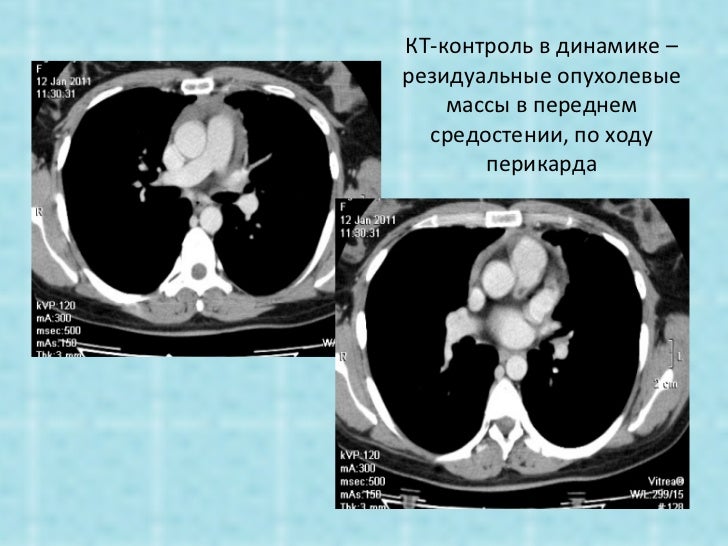

Неходжкинская лимфома с поражением вилочковой железы и надпочечников